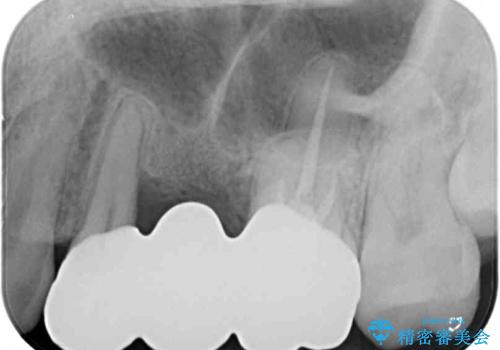

抜歯をしたことで、ずっと気になっていた異臭から解放されました。

手前の歯を削ってブリッジ治療とするのか、インプラントによる治療とするのか、悩んでいらっしゃいましたが、奥歯の銀歯もセラミックにしたいとのことで、ブリッジ治療を選択されました。